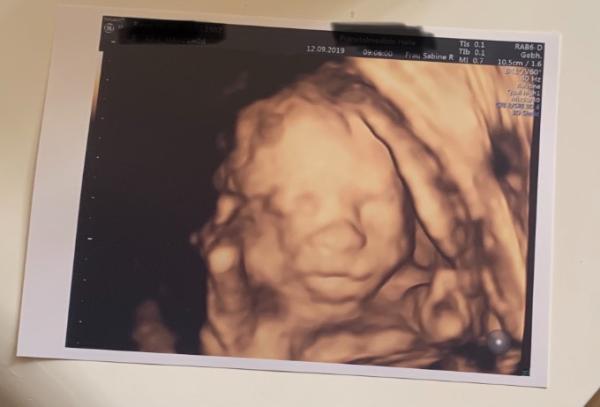

Huhu ihr Lieben, ich war heute zur Feindiagnostik und es wurde alles nochmal gecheckt, vor allem weil ich Montag erst die Blutung hatte. Der Kleinen gehts super, ist zwar zart aber top fit. Ich habe aber immer noch einen kleinen Saum der Plazenta am Muttermund und der könnte für diese Schmierblutungen verantwortlich sein. Ist aber wirklich nur ein kleiner Saum, der sich noch hochziehen kann. Allerdings wurde noch was anderes festgestellt. Ich habe eine Insertio velamentosa. Das heißt, die Nabelschnur setzt an der Eihaut an und nicht am der Plazenta. Gut ist aber, dass keine Gefäße über den Muttermund verlaufen. Aktuell bedeutet das erstmal nichts, außer das die Entwicklung der Kleinen engmaschig kontrolliert werden muss und ich bei 31+0 nochmal zur Feindiagnostik muss. Danach wird entschieden, wann die Kleine geholt wird oder ob doch eine spontane Entbindung in Frage kommt. Bei dieser Diagnose ist der Kaiserschnitt oft unumgänglich und wird schon bei 37+0 gemacht, da ein Blasensprung an der falschen Stelle tödlich fürs Baby sein kann. Ich muss den Schock nun erstmal sacken lassen und irgendwie wird nun 16 Wochen die Angst mitschwingen. Liebe Grüße Nicole PS:ein Bildchen hab ich aber auch bekommen!

Bild zu Feindiagnostik mit Befund 😬 - Forum für Januar - Mamis